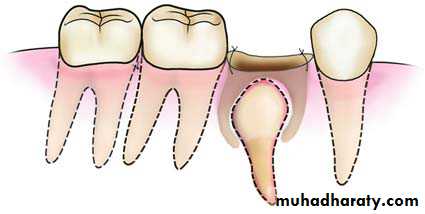

3- Extraction of Deciduous Molar that Embraces Crown of Permanent Tooth

Deciduous molar, whose roots embrace the crown of the succedaneous premolar

Envelope flap created and bone removed as far as the root bifurcationRoots of the molar sectioned with a perpendicular groove on the crown, which extends as far as the bifurcation

Removal of the distal portion of the tooth, which includes the crown and root, using forceps

Removal of the mesial portion of the tooth, which includes the crown and root

Suturing of the flap with interrupted sutures